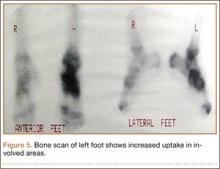

Bone scan showed increased uptake in the involved areas (Figure 5). Chest plain radiographs and CT showed no distant metastasis. An incisional biopsy was performed, and histopathology showed a malignant small round cell tumor, identified as Ewing sarcoma (Figure 6). An immunohistochemistry study demonstrated positive CD99 and negative cytokeratin, leukocyte common antigen, desmin, and synaptophysin.